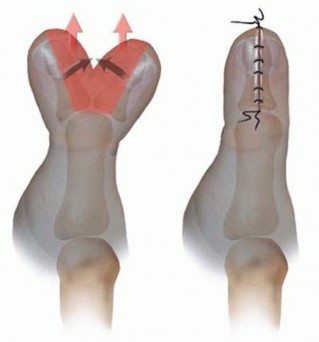

BILHAUT-CLOQUET PROCEDURE

TECH FIG 3 • Diagram depicting the Bilhaut-Cloquet procedure. (From Waters PM, Bae DS. Preaxial polydactyly. In: Pediatric Hand and Upper Limb Surgery: A Practical Guide. Philadelphia: Lippincott Williams & Wilkins, 2012:32-42.)